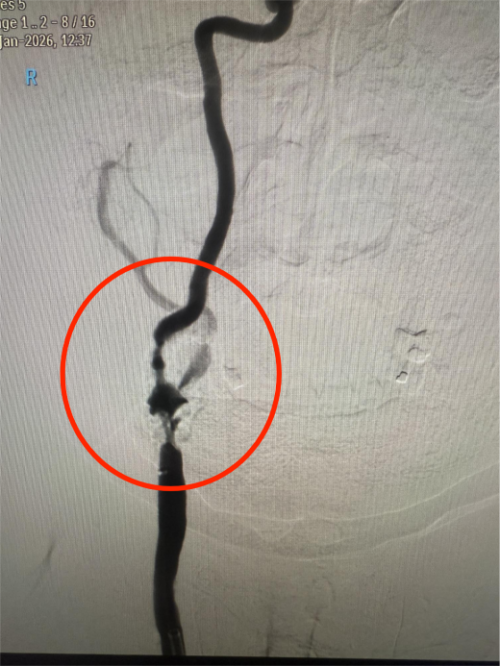

上图为该患者手术前重度狭窄的血管

传统药物保守治疗难以从根本上解决血管狭窄问题,无法有效规避脑梗死的风险。面对这一棘手局面,血管介入科马心龙副主任决定组织一场疑难病例讨论,同时邀请呼吸科、心内科、重症医学科等科室专家开展多学科会诊,全面评估患者的身体状况、血管条件及手术耐受性。同时,反复推演手术流程,细致排查术中可能出现的血压骤变、心律失常、斑块脱落、脑血管痉挛等风险点,并制定了针对性的应急处理方案。

在与患者家属充分沟通手术的高风险性及预期效果后,获得家属理解与手术意愿,医护团队决定为患者实施微创颈内动脉支架植入术。为保障手术安全,术前医护团队为患者优化基础疾病控制方案,精准调整血压、心率及凝血功能,做好各项术前准备工作。介入导管室提前调试数字减影血管造影(DSA)设备,备好远端保护装置、适配球囊、自膨式支架等精密器械确保手术高效开展。